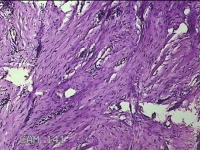

左耳赘生物

性别

女

年龄

23岁

临床诊断

纤维瘤?

一般病史

左耳皮肤起新生物2年。

标本名称

大体所见

灰白暗红色组织1.8x1.5x0.7cm,表面光滑,切面灰白粉红色,质软。

图1

良性病变。